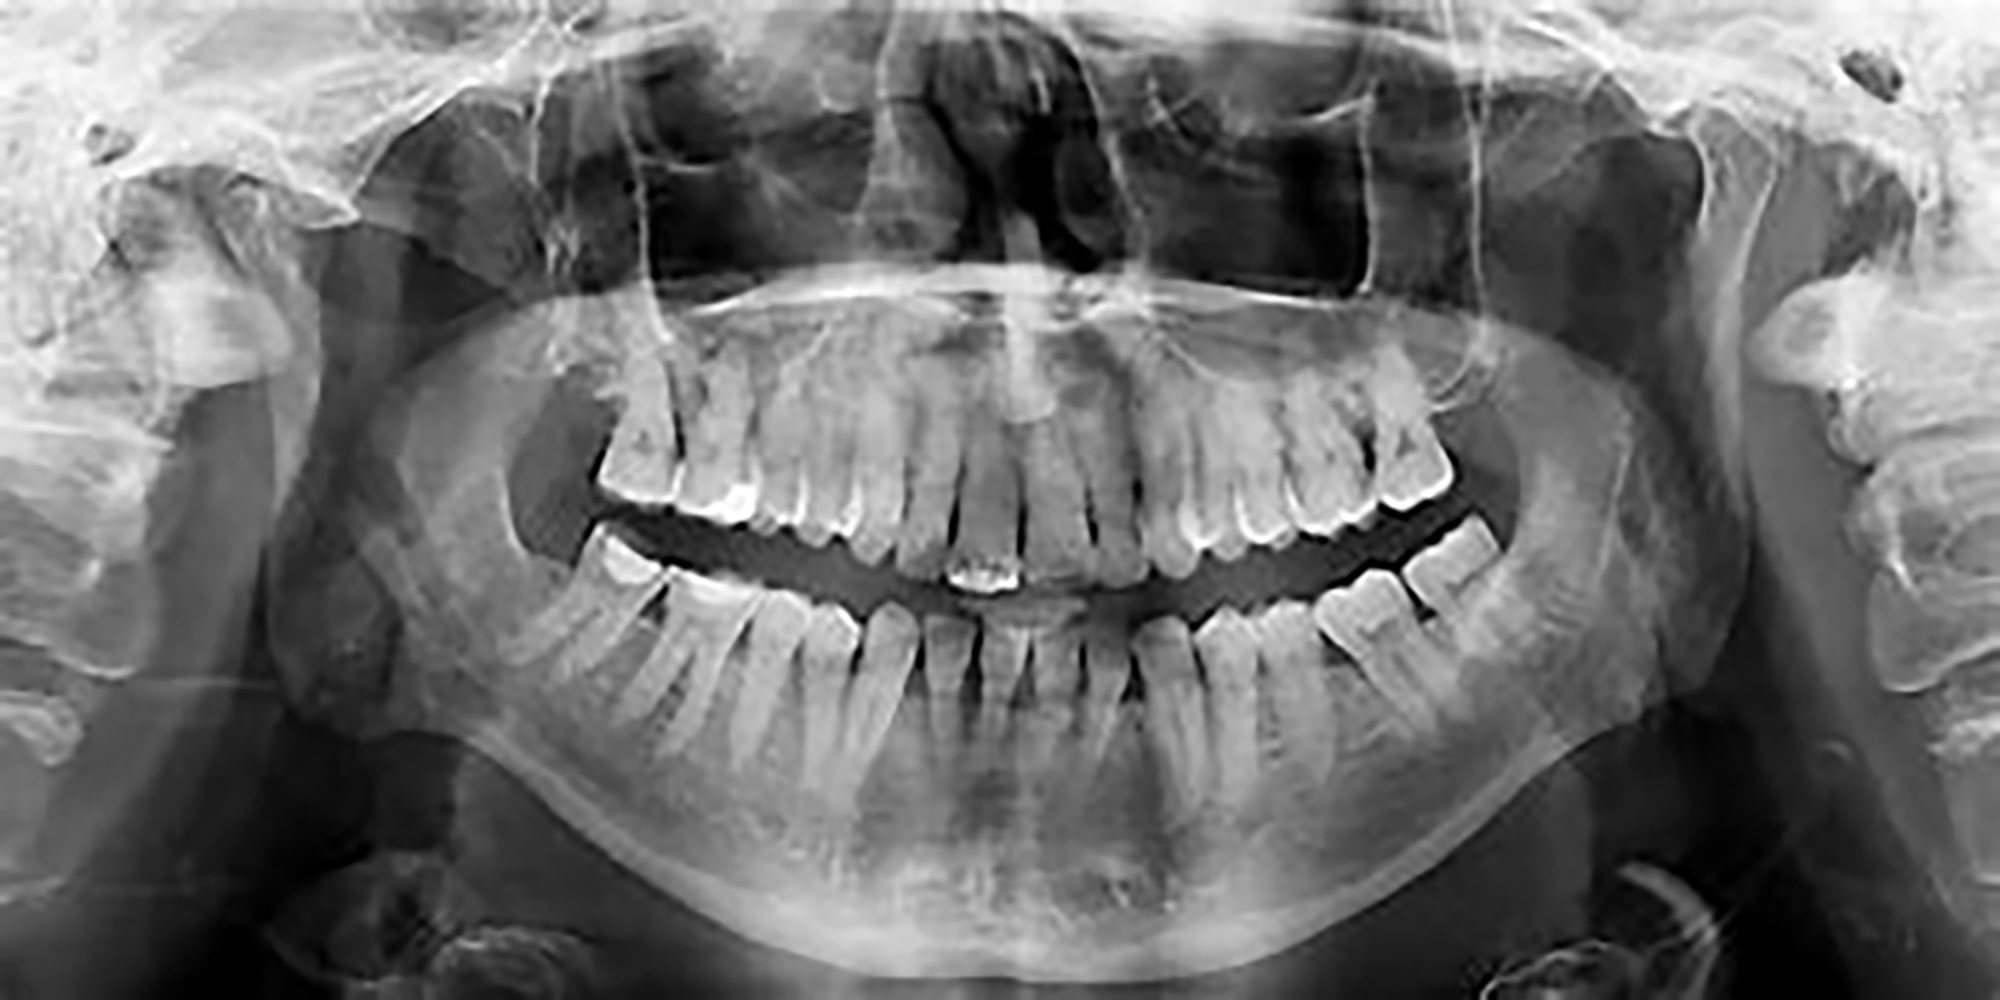

RADIOGAPHIE PANORAMIQUE

La radiographie panoramique utilise un appareil spécial qui prend une image de toutes vos dents supérieures et inférieures. Le résultat est une image en 2-D de votre bouche en 3-D.

Plus précis et complet que l’examen dentaire clinique, un orthopantomogramme permet de mettre en évidence les lésions des dents ou des gencives, invisibles ou peu visibles à l’œil nu, comme des débuts de caries, des kystes, des tumeurs ou des abcès.

Le panoramique dentaire met aussi en évidence les anomalies des dents de sagesse, ou bien des dents incluses.

La radiographie dentaire est également utilisée pour connaître la position des dents et leurs évolutions, notamment chez les enfants. Elle permet enfin d’effectuer un suivi de la perte osseuse et de l’état des gencives.